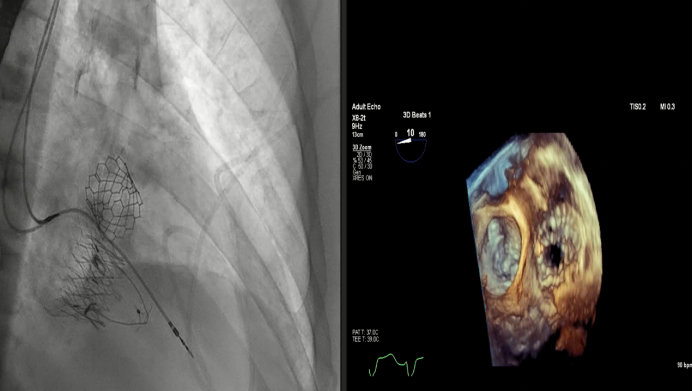

Dee Dee Wang教授分享了Henry Ford Hospital前4例Lux-Valve Plus的植入經(jīng)驗(yàn),并提示術(shù)中確定瓣葉夾持鍵的位置處于三尖瓣瓣環(huán)下方(右心室側(cè)),以及室間隔固定片與室間隔的相對位置關(guān)系是最關(guān)鍵的兩個步驟。使用經(jīng)胃底短軸切面,有時配合右室流入/流出道切面的X-plane就能較容易地獲取相關(guān)影像。由于Lux-Valve Plus對超聲影像的要求較低,手術(shù)過程會相對比較流暢。